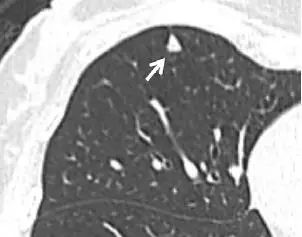

6. 毛刺状结节

图 6 左肺上叶层厚 1 mm 的 CT 横断面图像,显示一个可疑的实性毛刺状结节(箭头)。手术证实为浸润性腺癌。